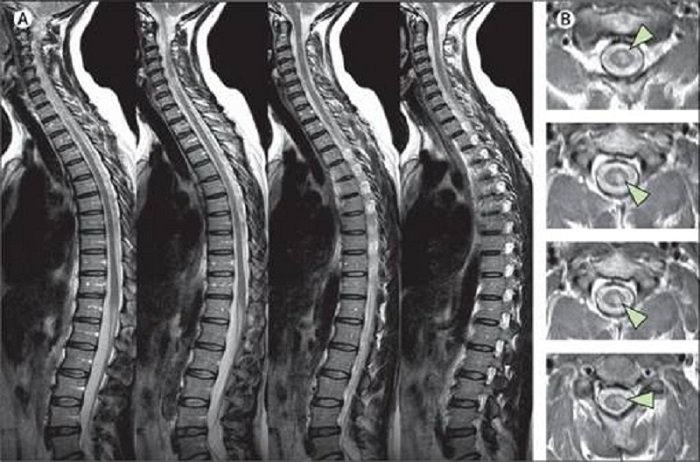

- Hình ảnh học: MRI cột sống thấy không giảm quá 50% chiều cao so với đĩa đệm bình thường lân cận, không gây hẹp ống sống > 30 – 40%